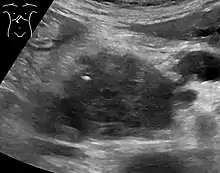

تُستخدم تقنيات التصوير الطبية كالتصوير المقطعي المحوسب والتنظير بالموجات فوق الصوتية في التشخيص والمساعدة في اتخاذ قرار إذا كان الورم يُمكن إزالته جراحيًا (قابلية استئصاله)[64]، ففي تباين التصوير المقطعي المحوسب يُظهر سرطان البنكرياس زيادة تدريجية في امتصاص مادة التباين الشعاعي، وذلك يختلف عن الإزالة السريعة التي تُرى في حالة البنكرياس الطبيعي، أو البطيئة التي تُرى في حالة التهاب البنكرياس المزمن.[67] يمكن أيضًا استخدام التصوير بالرنين المغنطيسي والتصوير المقطعي بالإصدار البوزيتروني[68] وكذلك يُمكن أن يكون تصوير البنكرياس والأوعية الصفراوية بالرنين المغناطيسي مفيدًا في بعض الحالات[65]، يُعد تخطيط الصدى البطني أقل حساسية وربما يفقد الأورام الصغيرة لكنه يُمكنه التعرُّف على السرطانات التي تنتشر إلى الكبد وتتكون من سائل في التجويف الصفاقي(استسقاء بطني)[64]، لذلك يمكن استخدامه للفحص الأولي السريع والرخيص قبل التقنيات الأخرى.[69]

يمكن استخدام الخزعة -التي غالبًا ما يتم توجيهها بواسطة الموجات فوق الصوتية بالمنظار- عندما يكون هناك شك بشأن التشخيص، ولكن التشخيص النسيجي ليس مطلوبًا عادةً للمضي قدمًا في إزالة الورم عن طريق الجراحة.[64]